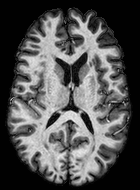

We observed that memberships predicted with an FC layer result in more false positives compared to a fully convolutional network. An example is shown in Fig. 2, where lesion memberships are generated from MPRAGE and FLAIR using the proposed model of convolutional pathways and a comparable model where the last convolutional pathway after concatenation (see Fig. 1) is replaced with a FC layer predicting voxel-wise memberships. The membership image generated with an FC layer, although being close to inside the lesions, has high values () in the left and right frontal cortex where the FLAIR image shows some artifacts. However, the membership obtained with the proposed method shows relatively low values near the frontal cortex.

With FC layer, voxel-wise predictions are performed for each voxel on a new image. Therefore the prediction time for the whole image comprising millions of voxels can take some time even on a GPU, as mentioned in Wachinger et al. (2017). In contrast, with fully convolutional prediction, lesion membership estimation of a mm3 MR volume of size takes only a couple of seconds. Note that although patches are used for training, the final trained model contains only convolution filters and does not depend in any way on the input patch size. Therefore during testing, the lesion membership of a whole 2D slice, irrespective of the slice size, is predicted at a time by applying convolutions on the whole slice. Without an FC layer, the images need not be decomposed into sub-regions, e.g., Kamnitsas et al. (2017). Consequently, there is no need to employ membership smoothing between sub-regions. In addition, since the training memberships, generated by Gaussian blurring of hard segmentations, are smooth, the resultant predicted memberships are also smooth (Fig. 2 last column).